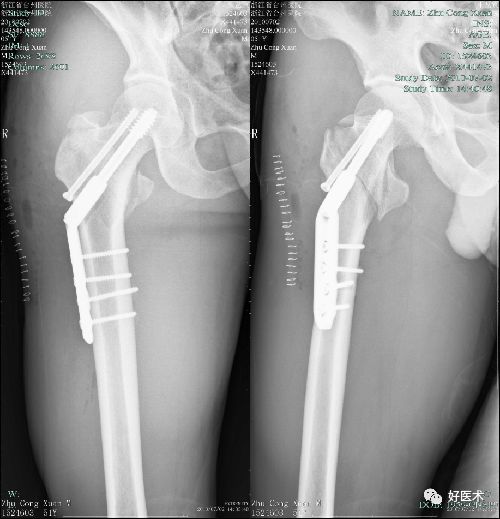

让老年患者告别“最后一次骨折” 海北州二院创伤中心进入微创时代仔细查体并结合患者影像记录制定手术方案,与当地医生交流讨论、充分评估手术风险、取得患者及家属同意后,制订了微创治疗闭合复位PFN... 在微创治疗出现前,业内常称该处骨折为“老年人的最后一次骨折”。随着生活水平的提高,超高龄股骨粗隆间骨折患者逐渐增加,如何提高围术...